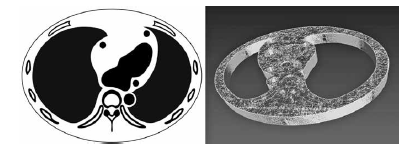

ここでは、冠動脈造影CTのための胸部ファントムの作成方法について解説する。はじめに図2aのように大まかな断面画像をドローイングツールで作成し、NIH ImageJ3)で読み込む。ここから、後述する様々な濃度の素材を封入するための空間を形成しながらボリュームデータ化していく。なお、頭尾方向における解剖構造の変化を考慮したほうがより忠実なファントムを作ることができるが、手間を省きたい場合には頭尾方向に変化のない、金太郎飴のような構造とする。また、関心のあるパーツのみを別で3Dで造形して挿入するということもできる。今回は冠動脈の部分のみ3次元的な変化を持たせるために別パーツとして造形した。その後、3D Slicer4)のModel makerプラグインを用いて、ボリュームデータを図2bに示すようなメッシュ―データに変換し、STLファイルとして保存する。

a 断面図

b メッシュ化した3Dデータ